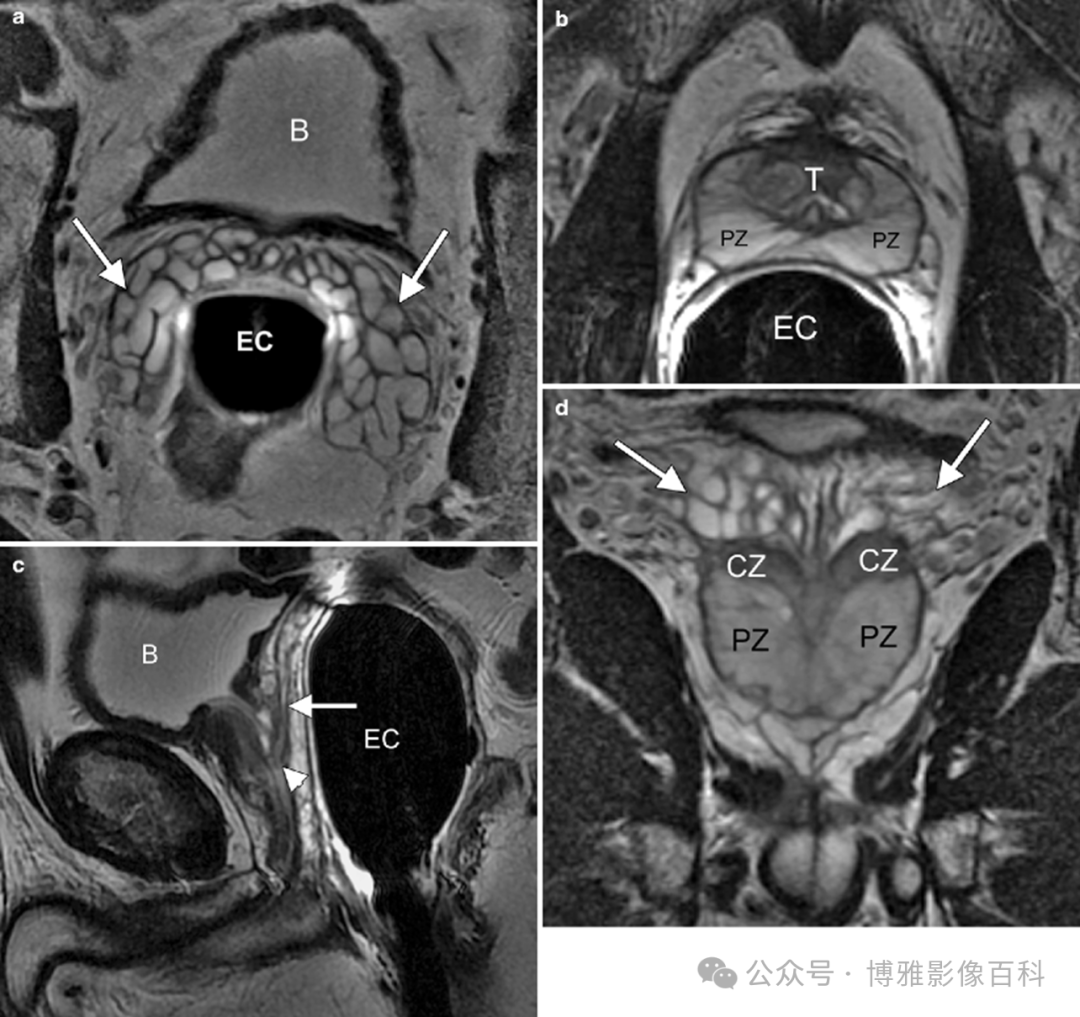

前列腺良性增生患者的轴向T2 图像,其他方面正常。外周带是一薄层均匀的高信号,边界清晰连续性的低信号包膜。移行带通常表现为不均匀中等信号,病灶被边界清楚的BPH良性前列腺增生结节所取代。精囊具有均匀T2高信号。未见淋巴结肿大。